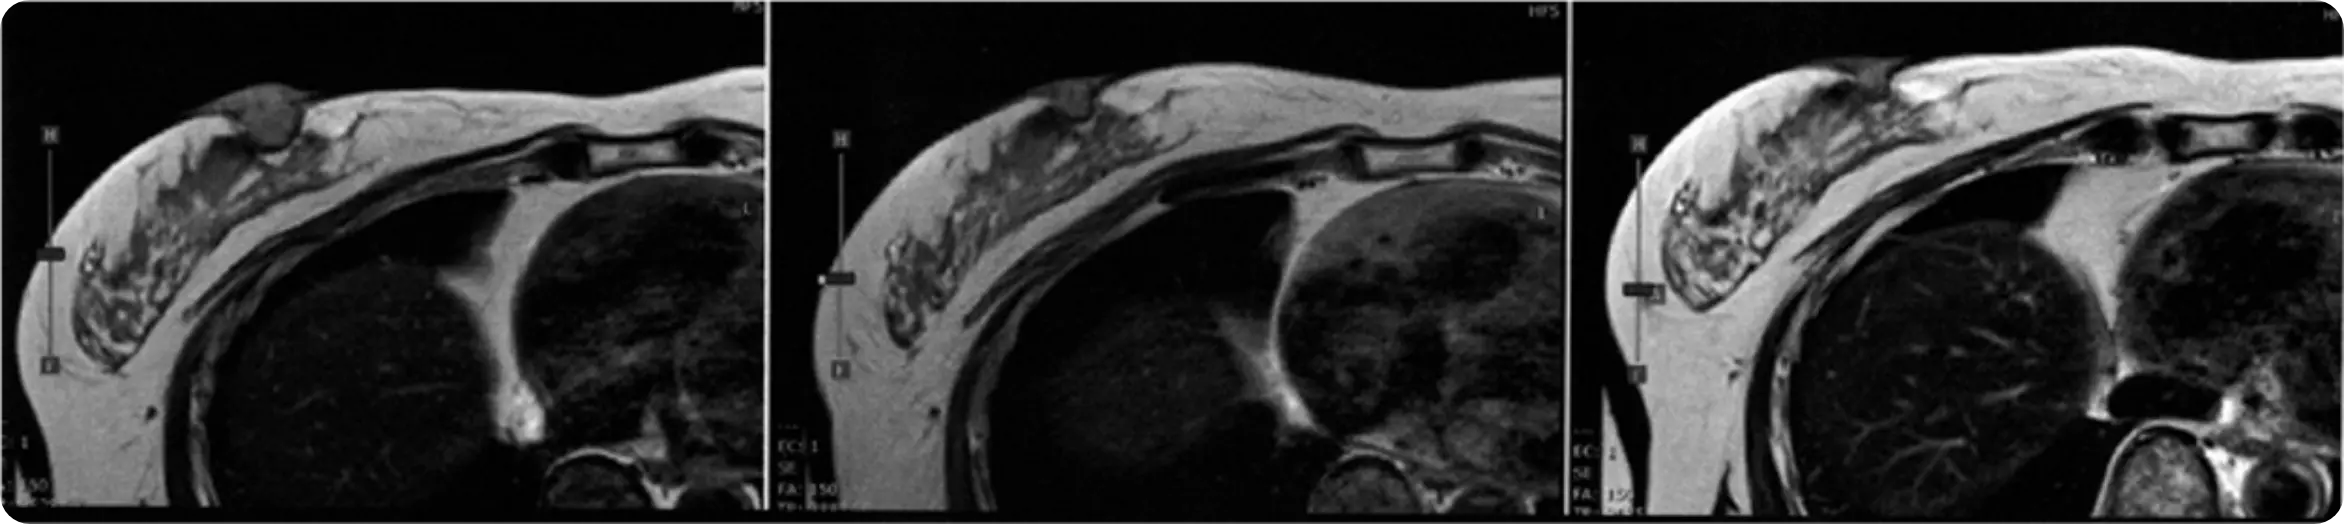

치료를 받지 않은 3B기 유방암을 가진 59세 일본인 여성 환자에게, 해당 적응증으로는 세계 최초로 BNCT 치료를 시행했습니다. MRI 검사 결과, 종양의 크기는 BNCT 시행 전 20mm에서 1개월 후 13mm, 2개월 후 10mm로 감소했으며, 3개월 시점까지 안정적으로 유지되었습니다. 환자는 종양의 촉감이 부드러워졌다고 보고하여 임상적 유효성을 시사하였습니다. 현재까지 주변 정상 조직에서의 이상 반응은 관찰되지 않았습니다.

MRI 촬영 전: 20mm

2개월 후: 10mm

3개월 후: 10mm